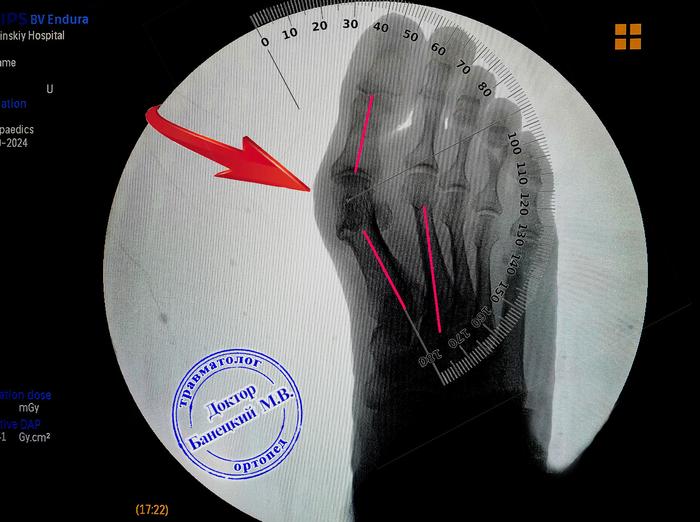

Оперативные методы лечения Hallux Valgus

Рекомендуется рассмотреть хирургическое вмешательство, если консервативные меры не принесли облегчения. Одним из распространенных методов является остеотомия, при которой изменяется форма костей, что позволяет вернуть пальцы в правильное положение.

Минималистичные процедуры, такие как артроскопия, обеспечивают менее инвазивный подход, что уменьшает время восстановления. Такой метод используется для устранения боли и удаления костных наростов, не требуя значительных разрезов.

При наличии тяжелых деформаций может понадобиться хирургия с фиксацией с помощью металлоконструкций. Это поможет обеспечить стабильность в восстановительном периоде.